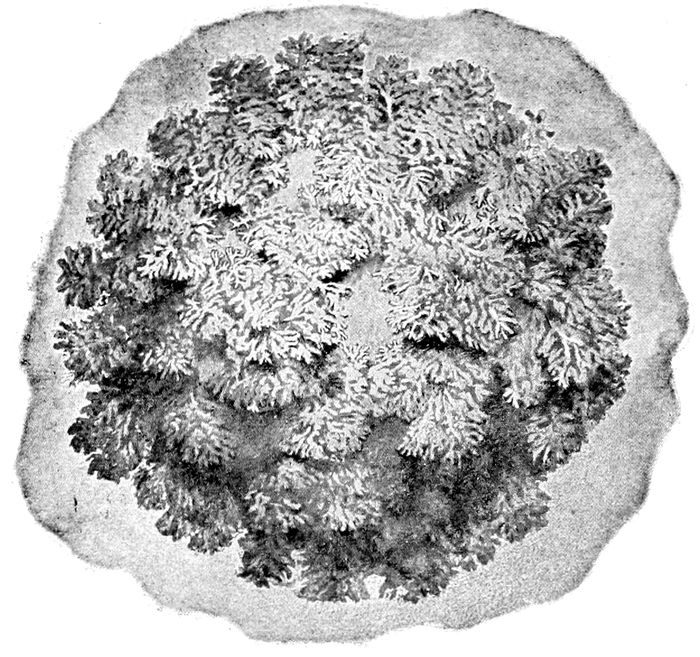

The chorionic villi about the third week of pregnancy |

Fig. 15.—The chorionic villi about the third week of pregnancy. (Edgar.)